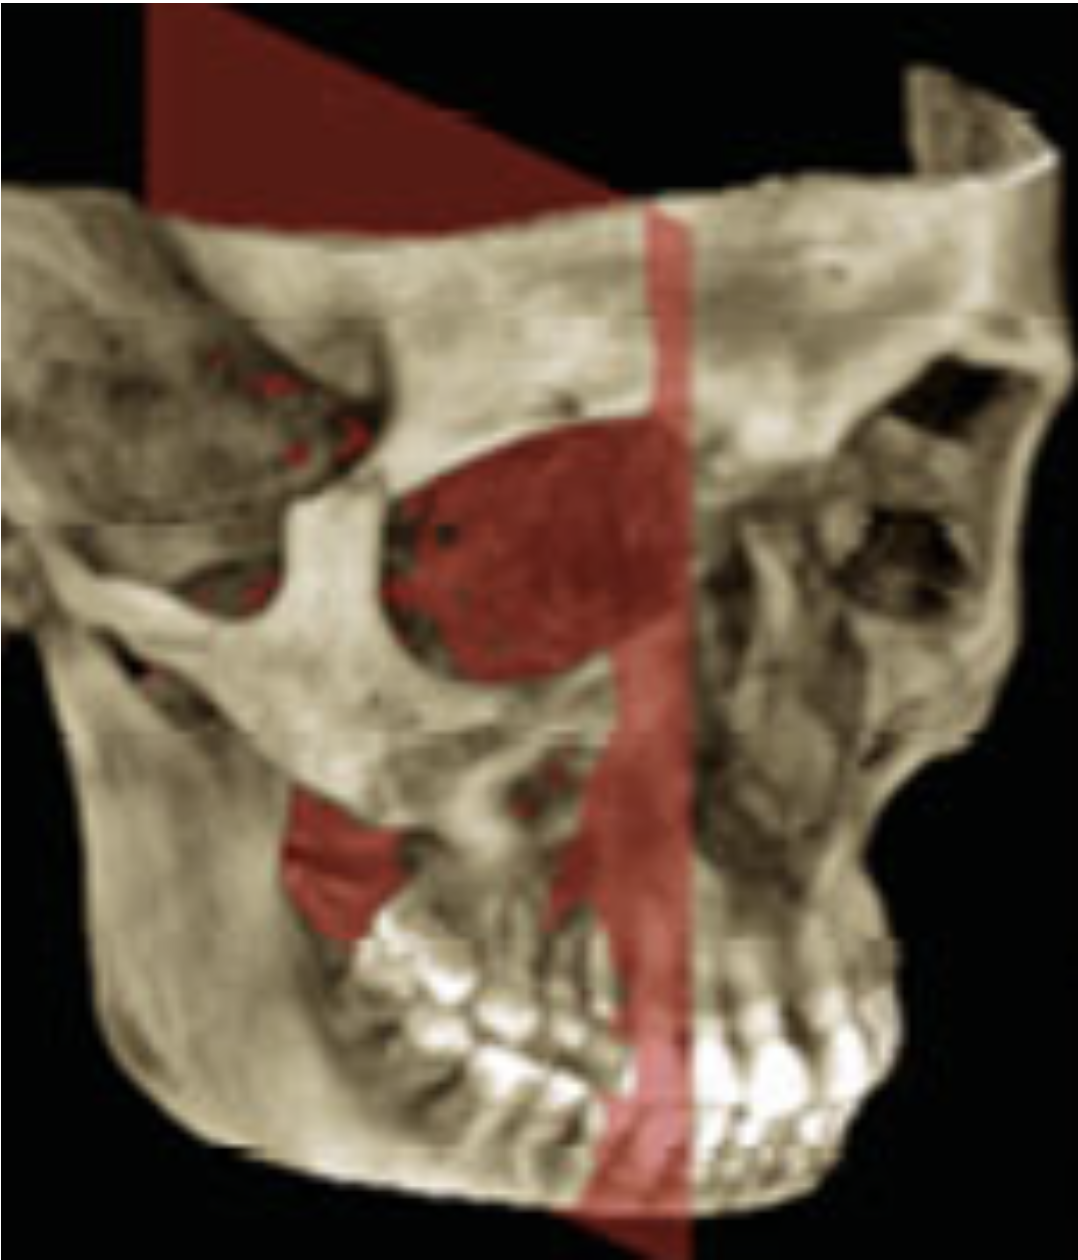

14

Label the different sinuses

Blue=Frontal Sinus

yellow=Ethmoid Sinus

Red=Sphenoid Sinus

Green=Maxillary sinus